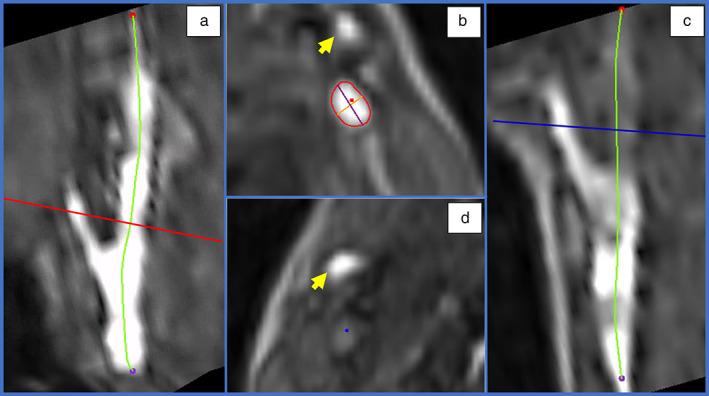

Three observers assessed IJVs on patency and created automatic centerlines from which diameter and patency were analysed perpendicular to the vessel at every 4 mm starting at the level of C2.

3 位观察者评估 IJVs 的通畅性,并从自动中心线创建直径和通畅性,以垂直于每个 4mm 处的血管,从 C2 水平开始进行分析。